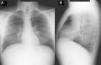

Case ReportA 40-year-old male diagnosed with N-P disease with hepatic and pulmonary affectation. Personal history included hepatosplenomegaly diagnosed at the age of 6–7 months. The patient was hospitalized at the age of 6 due to symptoms of asthenia, anorexia, deterioration and fever. Posteroanterior and lateral (PA-L) chest X-rays revealed diffuse reticular pattern. Given the radiographic findings and presence of hepatosplenomegaly, deposition disease was suspected. Rectal mucus and hepatic biopsies were suggestive of N-P disease (lipid-laden macrophages were observed). Neurological examination and respiratory function tests were normal. The diagnosis was confirmed when the patient was 20 using skin biopsy with fibroblast cultures, which confirmed a marked acid sphingomyelinase (ASM) deficiency characteristic of N-P disease that, supporting the clinical diagnosis, would be type B. At the age of 38, a molecular diagnosis revealed two mutations in the SMPD gene (heterozygosis in mutation p.R608del). The patient currently continues to be seen at the pulmonology and hepatology outpatient consultations, and he presents intermittent jaundice and maximal exertion dyspnea (MRC scale 0). On physical examination, minimal bibasilar crackles, subconjunctival jaundice and hepatosplenomegaly are observed. Neurological examination is normal. In the work-up, the most noteworthy results are: total bilirubin 4.17mg/dl; GOT 38IU/l; GPT 45IU/l; total cholesterol 221mg/dl. Lung function tests show a normal ventilatory pattern (FVC 3.84 [87.7%]; FEV1 3.13 [86%]; FEV1/FVC 81.58%; TLC 5.26 [81.8%]) and a mild alteration in the gas exchange (DLCO 57.5%). Radiographic findings on PA-L chest X-ray (Fig. 1A and B) include diffuse reticular interstitial affectation observed in the pulmonary parenchyma, predominantly in the middle and lower fields. HRCT (Aquilion Toshiba, 64-detector) (Fig. 2A and B) demonstrated diffuse ground-glass affectation, although predominantly in the lower lobes with subpleural septal thickening in the peripheral and mediastinal pleura and scissurae. No mediastinal or hilar lymphadenopathies are observed. The patient currently follows no type of treatment and only presents pulmonary and hepatic affectation with no central nervous system affectation.